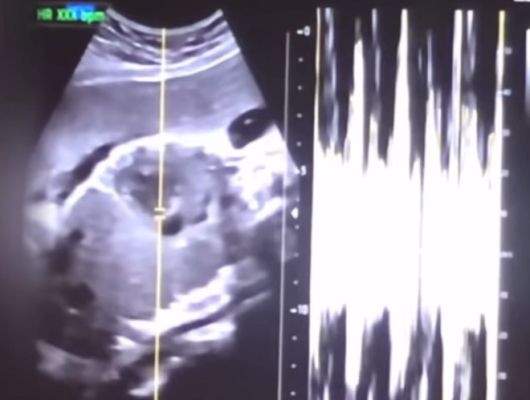

낙태한 산모의 유튜브 동영상에서 캡쳐한 초음파 사진과 심박 그래프. [사진=서울중앙지검] |

이 사건은 권씨가 유튜브에 임신 36주 차에 낙태한 경험담을 게재하며 알려졌다. 논란이 커지자 보건복지부는 지난해 7월 경찰에 진정서를 제출했고, 경찰은 수사에 착수했다. 검찰은 사건을 송치받은 이후 윤씨 등에 대한 재조사를 거쳐 의료법 위반 혐의를 추가로 인지해 혐의를 적용했다.